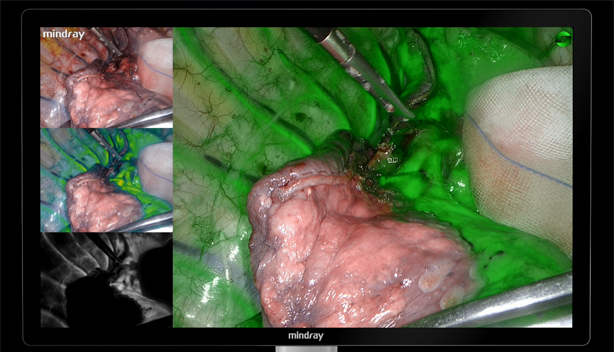

PercepciĂłn sensiblenavegaciĂłn precisa

El avance en la tecnologĂa de fluorescencia aumenta significativamente la sensibilidad de detecciĂłn y la estabilidad de la imagen de fluorescencia, lo que hace mĂĄs precisala navegaciĂłn.

El avance en la tecnologĂa de fluorescencia aumenta significativamente la sensibilidad de detecciĂłn y la estabilidad de la imagen de fluorescencia, lo que hace mĂĄs precisala navegaciĂłn.

Sensibilidad ultra alta de la fluorescencia

La doble optimizaciĂłn de excitaciĂłn e imagen reduce la sensibilidad de la captura de se?al de fluorescencia al nivel de los nanomoles, lo que favorece la detecciĂłn clĂnica de peque?as lesiones metastĂĄsicas con dosis bajas y ofrece una mayor capacidad de penetraciĂłn con la misma dosis.

Algoritmo de estabilizaciĂłn de la fluorescencia

VisualizaciĂłn precisa del ĂĄrea de imagen con verde de indocianina, eliminaciĂłn eficaz de la atenuaciĂłn de se?al causada por la distancia y la desviaciĂłn del ĂĄngulo, gran estabilidad de la fluorescencia y adecuada divisiĂłn de los mĂĄrgenes.

FusiĂłn de fluorescencias a nivel de pĂxel

El estricto control del proceso de montaje ayuda a obtener la fusiĂłn y alineaciĂłn pĂxel a pĂxel de la imagen de luz blanca y fluorescencias. La imagen de fluorescencias con detalles de textura de luz blanca tambiĂ©n puede ayudar en todo el proceso quirĂșrgico guiado por fluorescencia

Casos clĂnicos

EvaluaciĂłn de perfusiĂłn sanguĂnea en anastomosis colorrectal